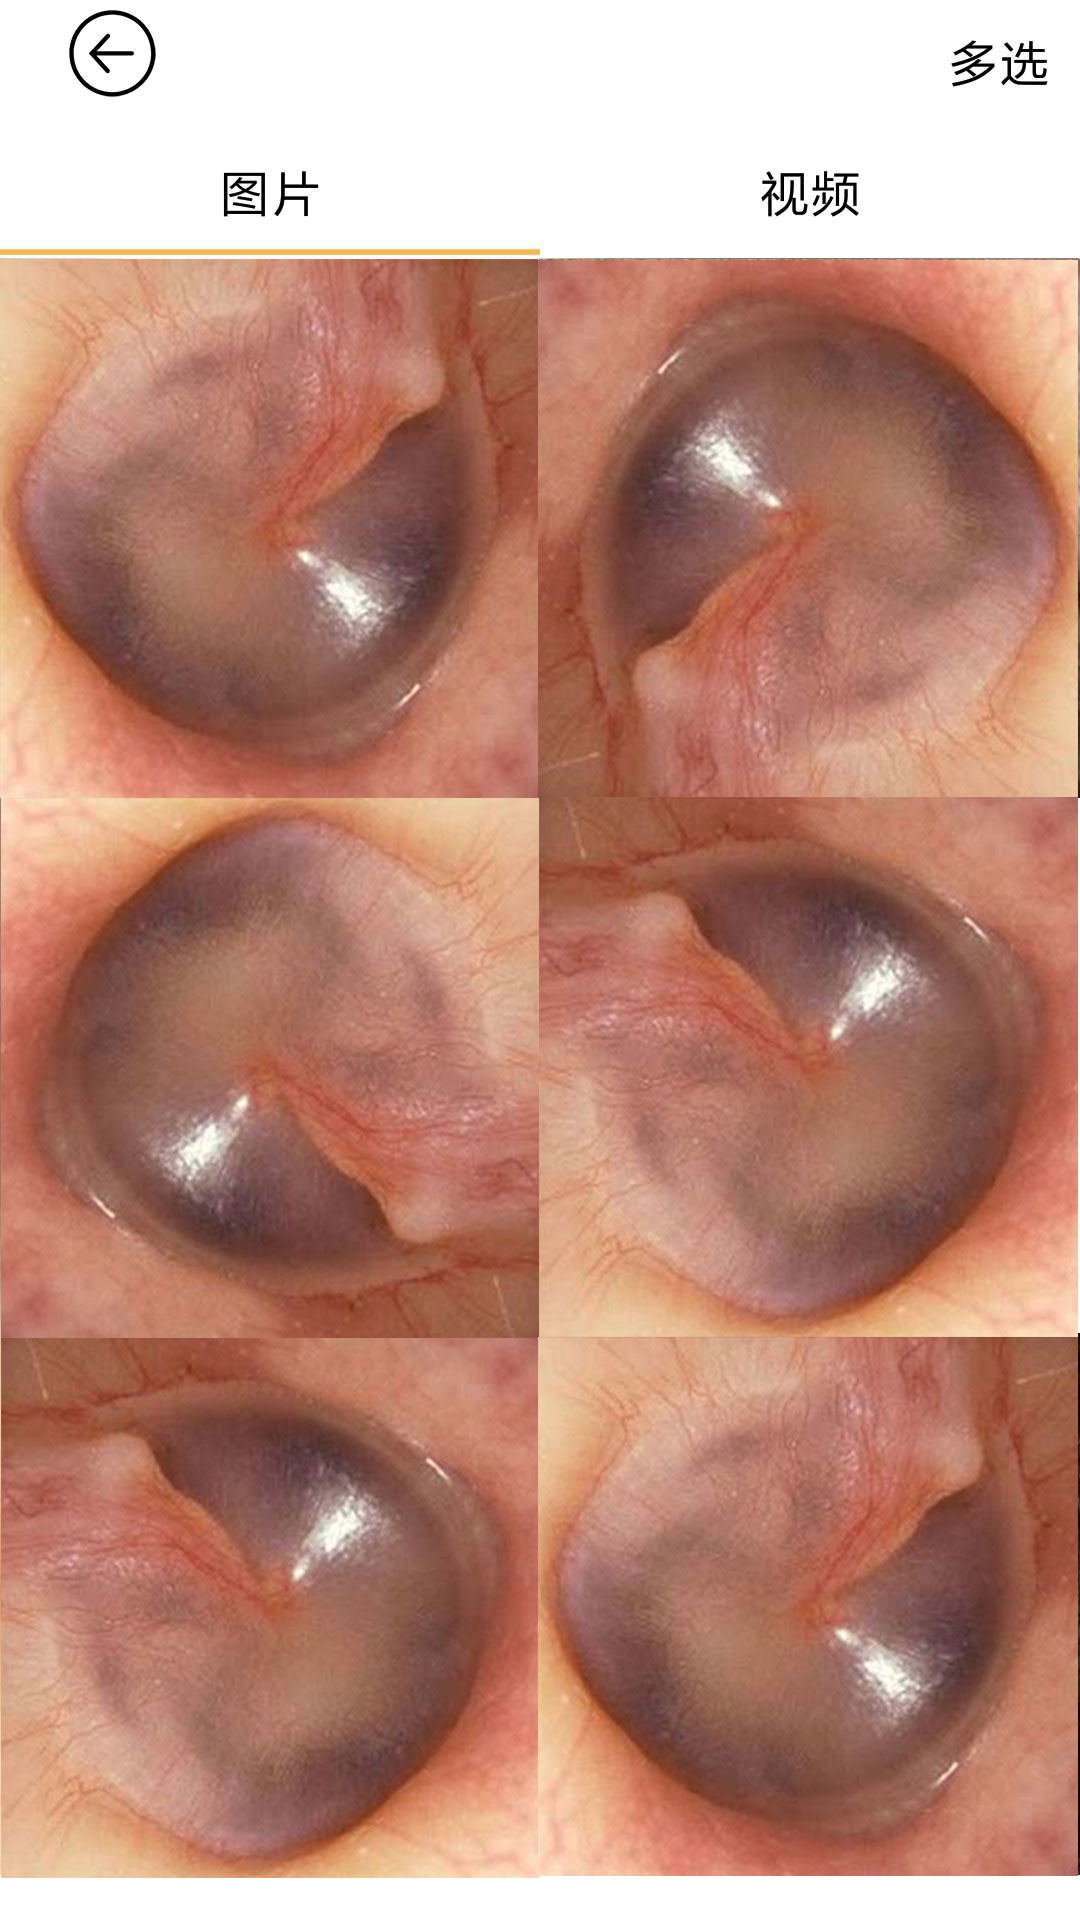

“bebird是一款專業(yè)個(gè)人健康護(hù)理類App,通過(guò)wifi與bebird可視采耳儀連接���,可以在App顯示清理耳道的實(shí)時(shí)畫面�����,個(gè)人可以輕松安全的享受采耳過(guò)程����。

采耳過(guò)程可拍照�、錄像,為防止采耳過(guò)程誤觸屏幕還設(shè)有采耳過(guò)程鎖屏功能����;